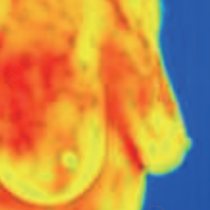

Diagnosis of breast disease

Abnormalities of structural characteristics identified on the breast thermal images are associated with diseases and cell activity. In different disease courses of the tumor tissue, there are significant characteristics of cell metabolism. With the aid of analyzing the infrared thermogram, early auxiliary screening can be achieved, and preventive and treatment measures can be taken earlier.